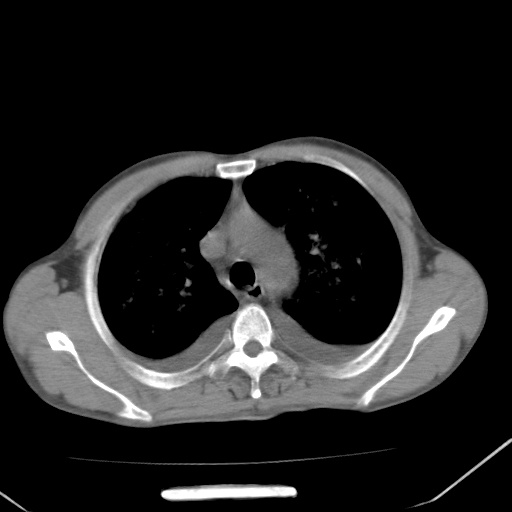

男、42岁、咯血3天。既往有甲亢、贫血、血尿蛋白尿史多年。血象:wbc:6.   中性粒:70.6%。

双肺野对称性磨玻璃影,分布于内中带,双侧胸水,患者有咯血。

左心房增大,考虑心衰,肺水肿。

双肺野广泛对称性磨玻璃影、实变影,以肺门为中心,主要分布于内中带,符合典型肺泡性肺水肿;伴双侧胸腔少量游离积液。结合患者既往病史且咯血就诊,支持多因素(尿毒症等)所致之肺水肿、肺出血、胸水;影像表现暂不考虑心源性水肿,且症状也不太符。需密切随诊结合临床治疗等进一步明确。

心影增大密度略低,双肺磨玻璃样高密度影及双侧胸腔积液,考虑心功能不全继发双肺肺水肿及双侧胸腔积液。心影密度略低,考虑贫血所致。